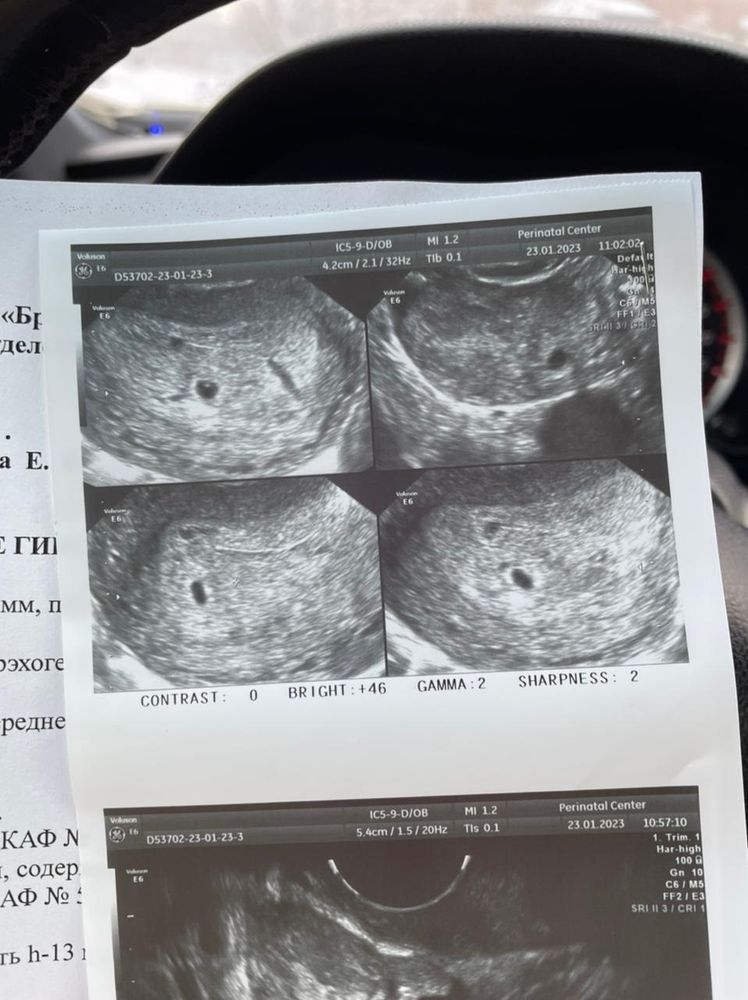

Хроническое воспаление маточных труб приводит к образованию жидкости в трубе. Анэхогенное образование это жидкость. Но вот тут смущает у вас жидкость ещё в позади маточном пространстве. Откуда она взялась. Вам и правда контроль УЗИ нужен. Плодное яйцо вероятно одно. Жёлтое тело одно значит овуляция одна была. Если бы разделился малыш они бы рядышком были мне кажется. В норме трубы не должны визуализироваться на УЗИ. И жидкость тоже не очень гуд кроме овуляции.

Могу предположить,что труба расширенна из-за гидросальпинкса,хроническое возможно воспаление,поэтому на узи из-за жидкости труба расширена. Насчет пя,я вижу одно,второе включение не понимаю, больше похоже,что оно в стенке матки,возможно полип или миома. У меня на фоне беременности миома появлялась. Тут однозначно только к врачу и наблюдение. Наугад не скажешь. Хотя,возможно и второе пя. Нужно повторное узи через время